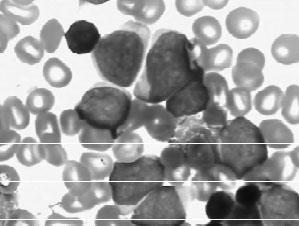

(4)急性粒—单核细胞白血病(M4)(见图3—8):按粒系和单核细胞系比例不同,包括下列4种类型。

图3—8 AML—M4骨髓象

1)M4a:原始和早幼粒细胞增生为主,原始、幼稚单核和单核细胞≥20%(非红系细胞)。

2)M4b:原始、幼稚单核细胞增生为主,原始和早幼粒细胞>20%(非红系细胞)。

3)M4c:原始细胞既具粒细胞系,又具单核细胞系形态特征者>30%(非红系细胞)。

4)M4E0:除上述特点外,还有粗大而圆的嗜酸颗粒及着色深的嗜碱颗粒占5%~30%(非红系细胞)。